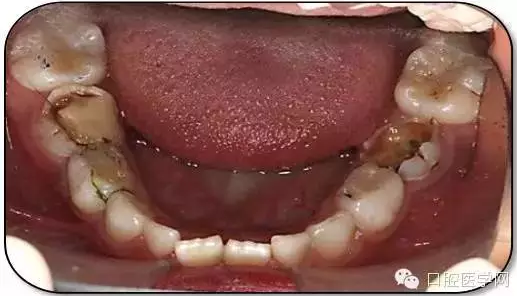

臨床檢查: 75OL齲洞, 舌側(cè)牙體完全劈裂斷端齊齦,探及大量軟化腐質(zhì)。頰側(cè)牙齦紅腫見瘺管,擠壓大量溢膿。叩(±),不松動。X線:75根管空虛,牙根吸收約1/2,根尖周及根分歧大面積透射影,35發(fā)育4期,骨硬板尚連續(xù);51殘根,唇側(cè)牙齦瘺管,叩(±),不松動。X線:51牙根吸收約1/2,根尖周低密度影。

85O、84DO充填體邊緣不密合,叩(±),不松動。84頰側(cè)牙齦略紅腫。X線:84遠(yuǎn)中根及髓室底完全吸收,根分歧透射影,近中根內(nèi)側(cè)見外吸收,44上方骨硬板連續(xù)。85近中根完全吸收,髓室底吸收,根分岐透射影,遠(yuǎn)中根管內(nèi)見根充影像。45發(fā)育4期,骨硬板連續(xù)。

55OL、65OL、74O、53DL齲洞,叩(-),不松動,齦無異常。

16OL、46OB、26O、36OB窩溝探及淺齲壞,叩(-),不松動,齦無異常。